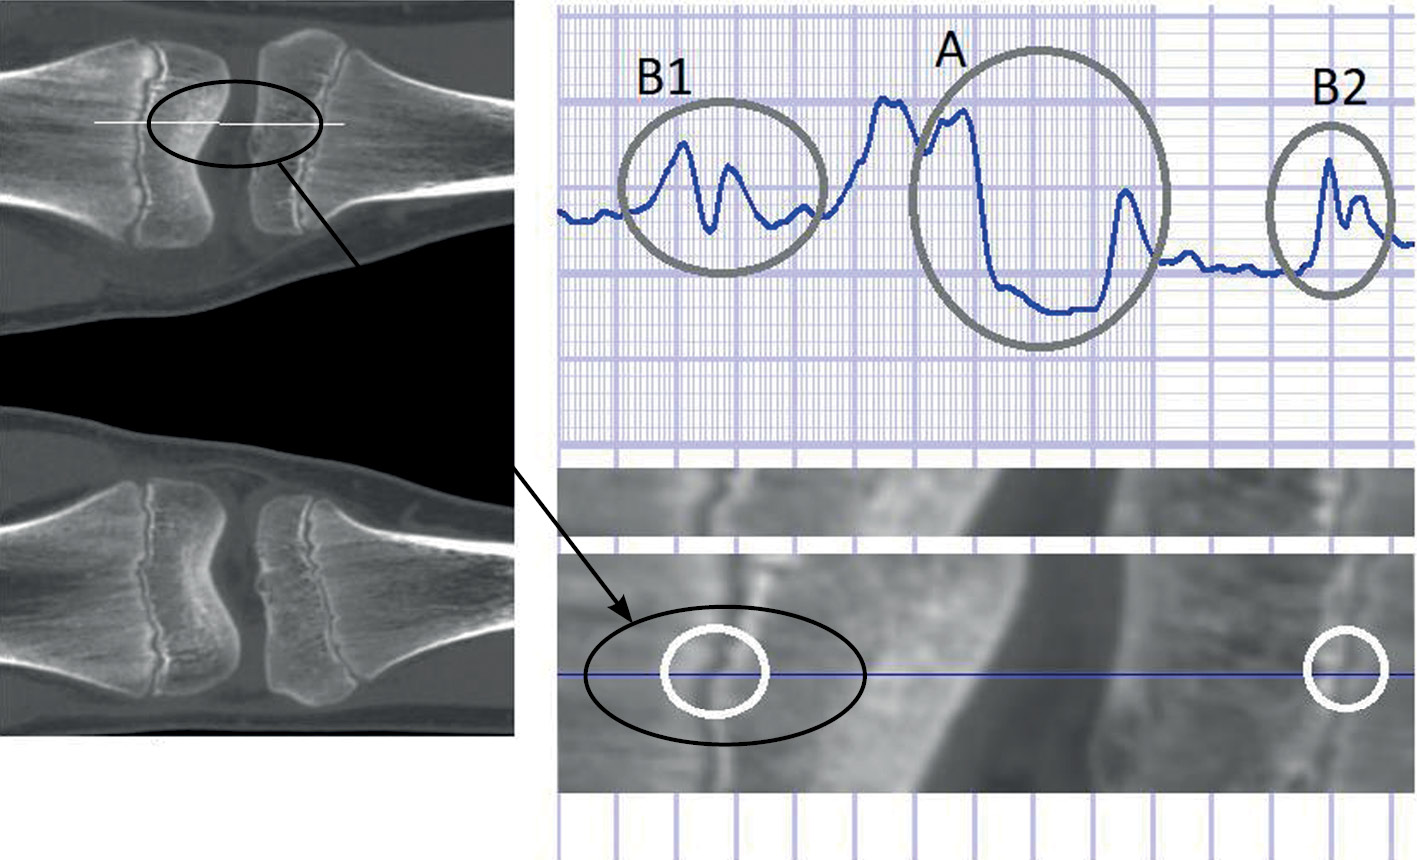

Сформированная в пространстве эпифизарная поверхность далее используется как самостоятельная диагностическая единица для оценки возраста. Согласно разработанному методу, выделяют две основные области ― область между костями (область «А», рис. 3) и область, примыкающую к эпифизарной линии (область «В»: «B1» ― для бедренной кости, «B2» ― для большеберцовой кости, см. рис. 3). Область «А» используется для калибровки и настройки процесса нормализации яркости, что позволяет привести все изображения любых случаев к одним и тем же нормализованным данным. Области «B1» и «B2» являются основными участками для расчёта возраста. Они (области «B1» и «B2», см. рис. 3) показаны как двумерные, однако расчёт и оценка свойств выполняются в трёхмерном пространстве, т.е. для всей поверхности эпифизарных пластин, причём и бедренной, и большеберцовой костей. Чем больше пик в областях «B», тем ближе возраст к 14(±1) годам. Отсутствие выраженного пика в областях «В» означает формирование эпифизарного сращения. Распределение значений пика яркости, связанного с плотностью костной ткани в данной области, в зависимости от его положения в трёхмерном пространстве для всей эпифизарной пластинки позволяет оценить возраст.

Рис. 3. Пример нормирования и вычисления свойств изображения при вычислении свойств эпифизарной линии (плоскости): А ― область между костями; В ― область, примыкающая к эпифизарной линии (B1 ― для бедренной кости, B2 ― для большеберцовой кости).

Fig. 3. Example of normalization and calculation of image properties when calculating the properties of the epiphyseal line (plane): A ― the area between the bones; B ― the area adjacent to the epiphyseal line (B1 ― for the femur, B2 ― for the tibia).